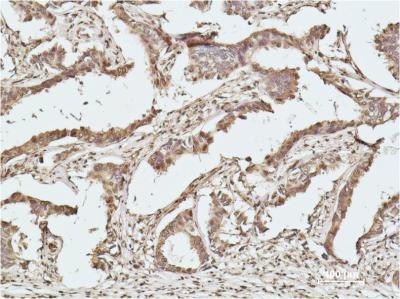

Product Image

IHC | 1/50-1/100 |

WB | 1/500-1/1000 |